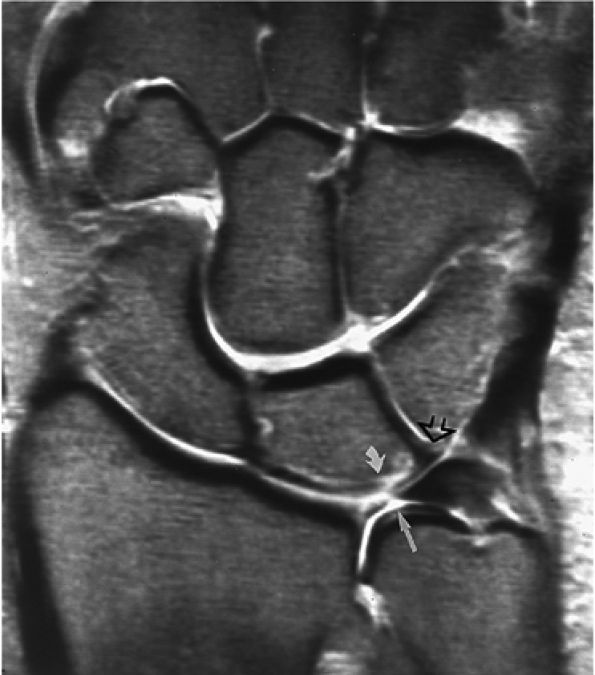

FIGURE 10.63 ● The long radiolunate or radiolunotriquetral (RLT) ligament. (A) The RLT ligament is divided into a radiolunate ligament and lunotriquetral component. The RLT ligament functions as a volar sling for the lunate. L, lunate; R, radius. Volar FS coronal T1-weighted arthrogram. FS axial T1-weighted arthrograms obtained at the level of the proximal (B) and distal (C) aspects of the radial styloid show the volar course of the RLT ligament (large arrows) from the radial styloid (R) inserting into the lunate (L) and blending with the volar portion of the lunotriquetral interosseus ligament. The lunate attachment of the scapholunate interosseous ligament volar fibers is deep to the lunate attachment of the RLT ligament (B). S, scaphoid; T, triquetrum; SL, scapholunate ligament.